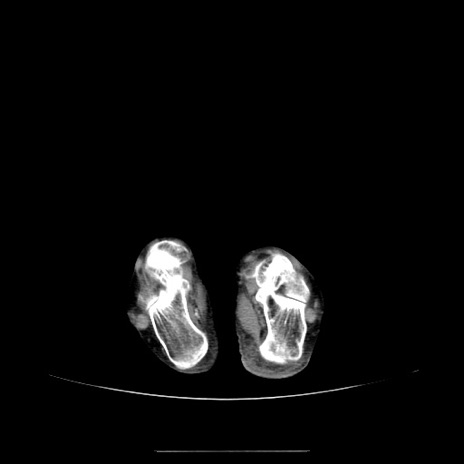

冠状断像